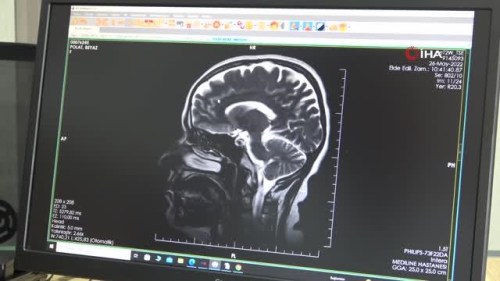

ELAZIĞ Elazığ Mediline Hastanesi Nöroloji Hastalıkları Uzmanı Oktay Kapan, 30 Mayıs Dünya MS Günü dolayısıyla açıklamalarda bulunarak, MS hastalığının erkeklere oranla kadınlarda 2 kat daha fazla olduğunu söyledi. Elazığ Mediline Hastanesi Nöroloji Hastalıkları Uzmanı Oktay Kapan, MS hastalığı hakkında açıklamalarda bulundu. 30 Mayısın Dünya MS Günü olduğunu aktaran Uzm. Dr. Oktay Kapan, "Halk arasında MS olarak bilinen multiple skleroz, hareket aksaklığı, kaslarda güçsüzlük, kısmi felç, dengesizlik, konuşma bozukluğu ve görme bozuklukları gibi farklı belirtiler ile birlikte kendini gösteren ataklar halinde erkeklere oranla kadınlarda iki kat daha fazla görülen bir rahatsızlıktır. Genç bayanları daha sık tutan bir rahatsızlıktır. Son zamanlarda sıkça görülen ve sıklığı giderek artan nörolojik bir hastalıktır. MS hastalığının belirtileri ve tedavisi kişiye özeldir. Benzer şekilde gelişen ve aynı bulguları seyreden iki hasta bulabilmek mümkün değildir. Hastalığın bireyin kendisi ve hastalar arasında farklı seyretmesi hastalığın zamanlamasını, beyinde tuttuğu yeri ve bulguların şiddeti farklı kılmaktadır. Genel olarak MS'li olgularda beynin veya omuriliğin kontrol ettiği bir fonksiyonun tam veya kısmi kaybı söz konusudur" dedi. "MS Belirtileri kişiye göre değişebilmektedir" MS hastalığının belirtilerinden de bahseden Uzm. Dr. Kapan, "MS hastalığının belirtileri kişiye göre değişebilmektedir. MS'li hastalar sayacağım belirtilerden herhangi birini, ataklar, düzelmeler veya yavaş yavaş gelişen seyir izleyerek yaşayabilirler. Bunlar, uyuşukluk, karıncalaşma, iğneleşme, kaslarda spazm, kas sertliği, kramp, ağrı, güç kaybı ve bu güç kaybı vücudun bir tarafındaki kol ve bacakta veya her iki bacakta birden olabilir, idrar kaçırma, idrara aşırı sıkışma, kabızlık, konuşma bozuklukları, cinsel fonksiyon bozukluğu, denge kaybı, bulantı, kusma, yorgunluk, depresif duygu durumu, kısa süreli hafıza bozukluğu ve yutma zorluğunu da sayabiliriz. MS'li bir hastanın ilk belirtileri kol ya da bacakta kuvvet azalması ve güçsüzlük şikayeti ile başlar. MS'li hastalar genellikle duygusal bozuklukları, bulanık görme, denge bozuklukları, çift görme gibi belirtilerle doktora başvururlar. MS hastalığının belirtilerinin her hastada birbirinden farklı olabileceğini akılda tutmak gerekir. En belirgin MS belirtileri halsizlik yüzde veya vücutta uyuşma, karıncalaşma, hissizlik, yorgunluk, denge problemleri, kas sertleşmesi, konuşma bozukluğu, bağırsak veya idrar torbası problemleri, dengesiz yürüme yani ataksi, cinsel işlev sorunları, ısıya hassasiyet ve kısa süreli hafıza sorunları şeklinde sıralanabilir. Aniden ortaya çıkan ve birkaç gün sürüp düzelen görme konuşma sorunları ya da kişinin yazısının kötüleşmesi gibi belirtilerde MS yani multiple skleroz hastalığının işareti olabilir. Bu tür hastalarda önemli olan erken tanı ve erken tedavidir" diye konuştu.